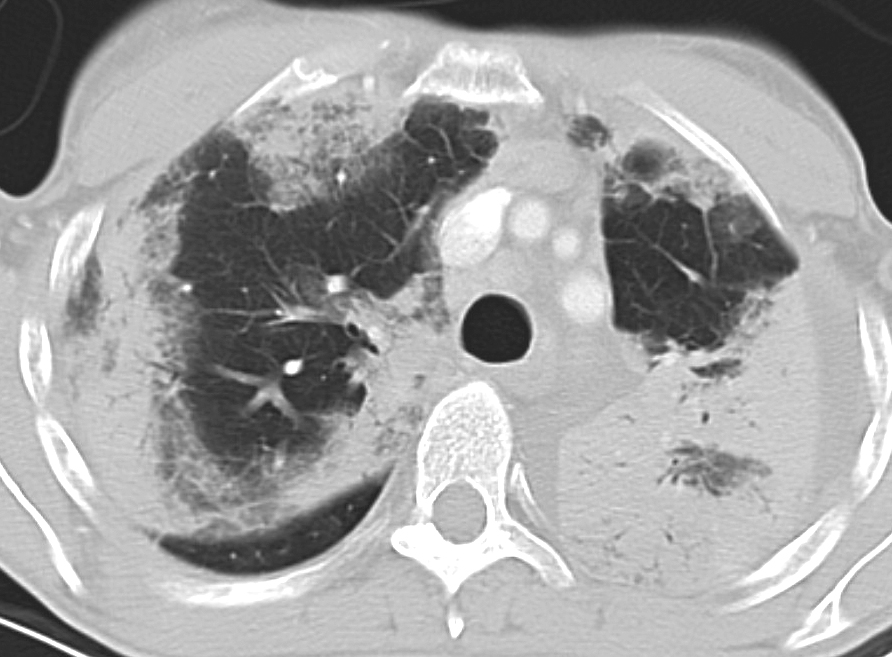

Eos Pneum (AEP) CT